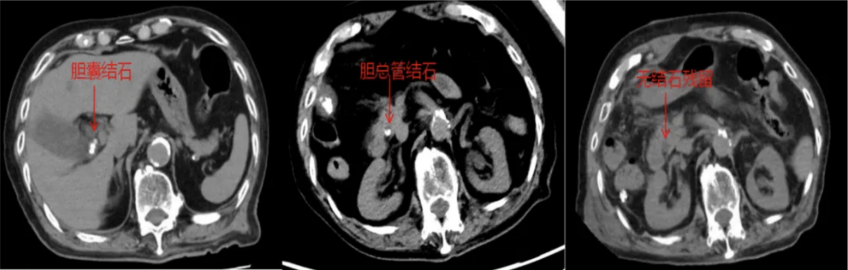

近日,100岁的陈爷爷突然右上腹剧痛、高烧不退,急诊确诊为:胆囊结石伴急性胆囊炎、胆总管结石伴急性胆管炎。老人免疫力差,感染像野火一样蔓延,再不动手术就可能休克甚至丧命,但传统开腹手术创伤大,术后并发症风险极高,对百岁老人来说更是风险堪比“走钢丝”,如何选择手术方式成为治疗关键。

经多学科团队综合评估后,2026年足球世界杯直播附属浦东医院肝胆外科主任王晓亮、主任医师李春生团队决定采用腹腔镜联合经胆囊管胆总管取石术(TC-CBDE)帮助老人渡过难关。

手术台上,医生先切除了穿孔坏疽的胆囊,再像“穿针引线”一样,通过胆囊管这个“天然隧道”,把胆总管里的结石一颗颗取出来。全程90分钟,未出现胆道损伤、出血等并发症。术后重症医学科蔡金芳主任团队监护治疗,为老人安全保驾护航。术后第二天转入普通病房,术后7日便康复出院。

这种技术有三大好处。一是不切开胆总管,传统手术切开胆总管后得插管引流,住院时间长且存在胆漏、胆管狭窄等风险,而现在通过胆囊管取石,能避免胆总管损伤,降低术后并发症。二是手术时间短、创伤小,腹腔镜微创切口小,对心肺功能较差的老人更安全;三是恢复快,术后无需长期带管,老人能早吃饭早活动,恢复速度远超传统手术。